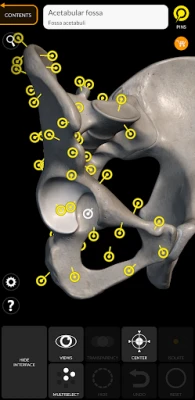

"Skeleton | 3D Atlas of Anatomy" is a next generation anatomy atlas in 3D which gives you availability of interactive highly detailed anatomical models!

Each bone of the human skeleton has been reconstructed in 3D, you can rotate and zoom in on each model and observe it in detail from any angle.

By selecting models or pins you will be shown the terms related to any specific anatomical part, you can select from 12 languages and show the terms in two languages simultaneously.

HIGHLY DETAILED ANATOMICAL 3D MODELS

• Skeletal System

• Accurate 3D modeling

• Surfaces of the skeleton with high resolution textures up to 4K

SIMPLE AND INTUITIVE INTERFACE.

• Rotate and Zoom every model in the 3D space

• Division by regions for a clear and immediate visual of each structure

• Possibility to hide every single bone

• Intelligent rotation, automatically moves the centre of rotation for easier navigation

• Interactive Pin allow visualization of the term relative to every anatomical detail

• Hide / Show interface, ideal for use on smartphones